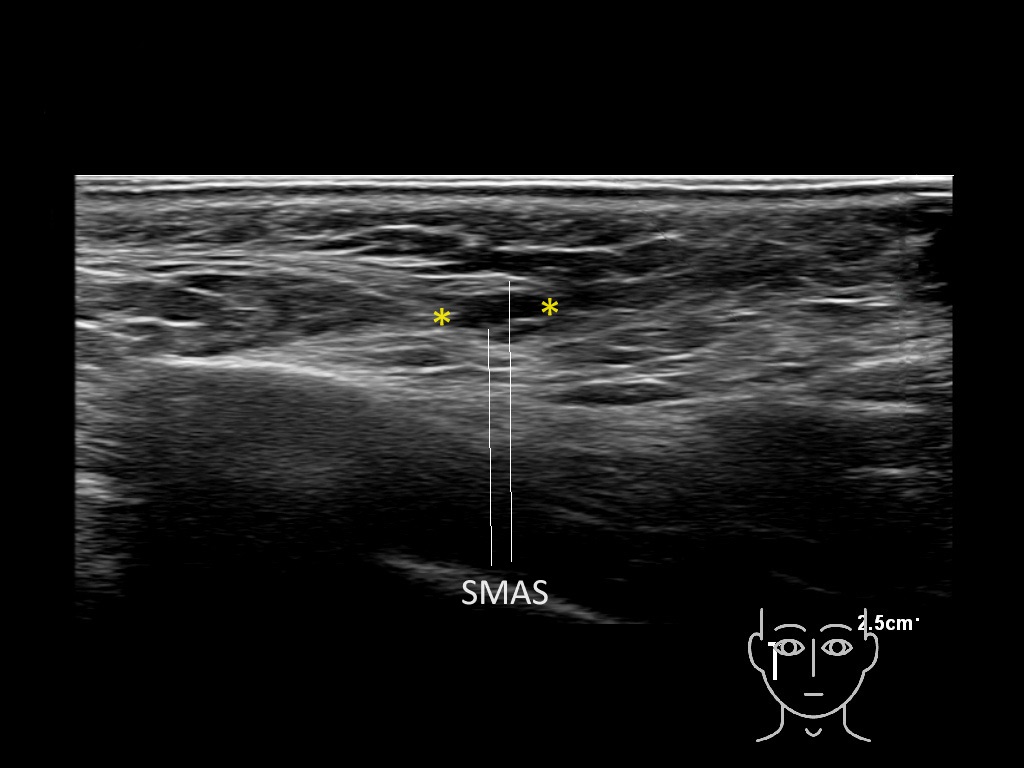

Filler deposits may end up unintentionally in the SMAS or fascial layers of the skin. Very often this will not lead to adverse events, however, adverse events ( nodules, migration / redistribution impaired muscle movement and smiling and malar edema) are are often related to filler ending up in the SMAS or fascia.

Study the first image to recognize the different layers. If you are sure about the layers, swipe to the second image to view the answer (if applicable).